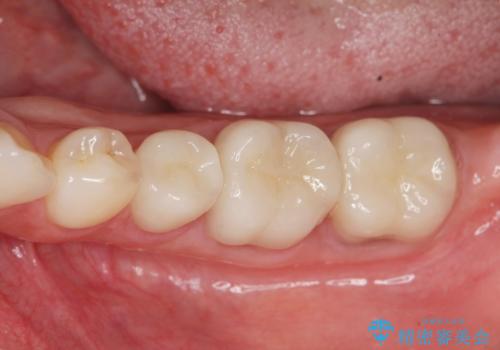

- 左下の歯が虫歯により崩壊し、歯ぐきからの出血も毎回歯ブラシを行う際に出ることから治療を求めて来院されました。

現在装着されているクラウンを除去したところ、クラウンマージンが歯肉縁下となり歯ぐきの炎症が認められたため再度オールセラミッククラウンを製作する前に歯周外科手術を行い歯ぐきの状態を改善しました。

- 45万円(仮歯×3・ファイバーコア×2・ジルコニアクラウン×3 歯周外科手術)費用は治療当時の料金となります